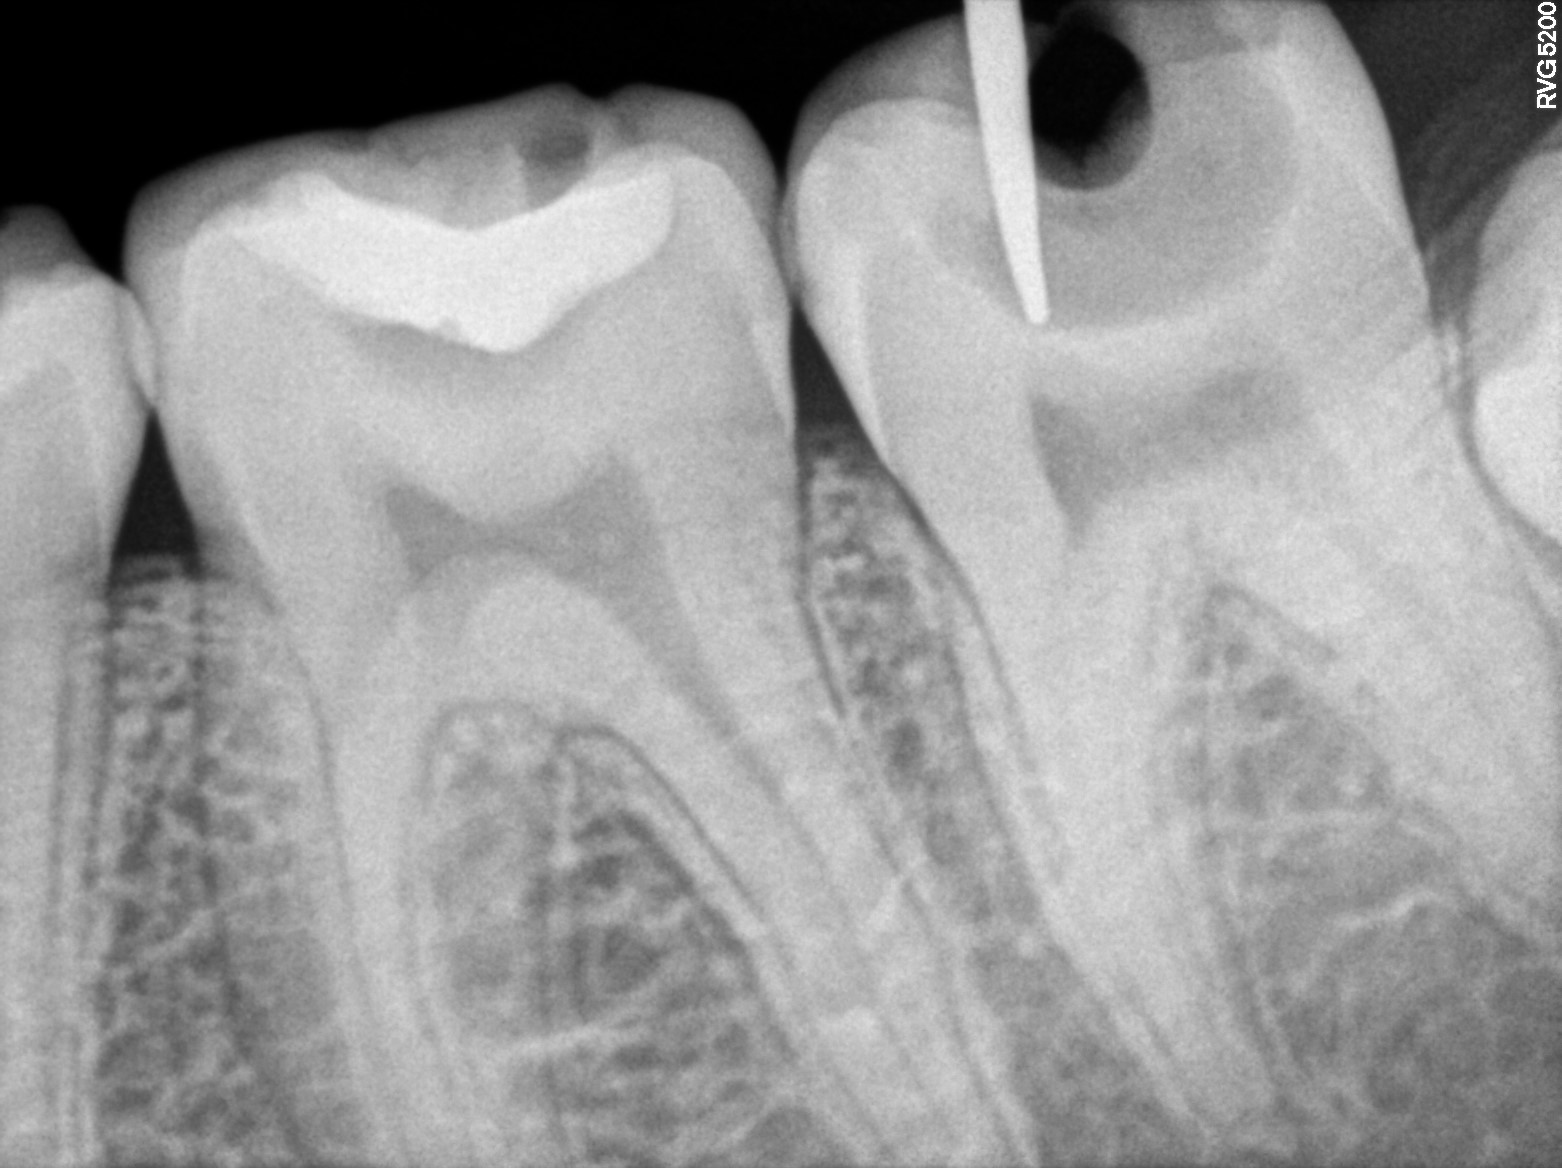

Dental Radiographs FHIR: DocumentReference · LOINC 24641-7

R53.jpg

24641-7